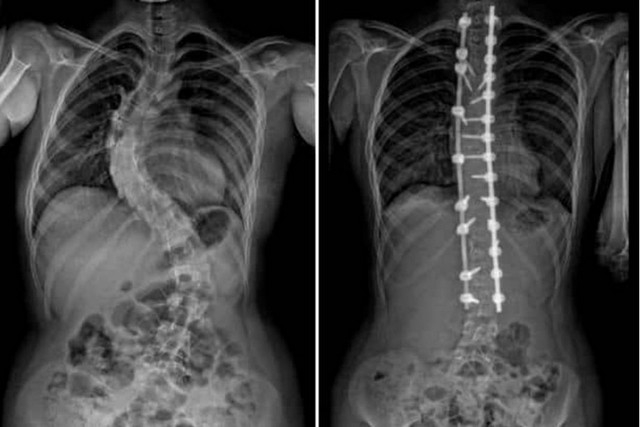

2. การถ่ายภาพเอกซเรย์ เพื่อตรวจสอบระดับความคดของกระดูกสันหลังและวัดมุมคอบบ์ (Cobb angle)

การวัดมุมคดองศากระดูกสันหลัง (Cobb Angle) มุมคอบบ์ (Cobb angle) ใช้วัดระดับความรุนแรงของกระดูกสันหลังคด

• น้อยกว่า 10 องศา – ถือว่าอยู่ในช่วงปกติ

• 10-20 องศา – เฝ้าระวังและตรวจติดตาม

• 20-40 องศา – อาจต้องใส่อุปกรณ์พยุงหลัง (Brace)

• มากกว่า 40-50 องศา – อาจต้องพิจารณาการผ่าตัด

3. การผ่าตัด (Surgery) – กรณีที่มุมคดเกิน 40-50 องศา หรือมีอาการรุนแรงที่ส่งผลต่อการหายใจ